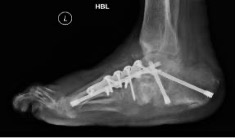

Despite adequate offloading, deformities may progress with bony instability resulting in ulceration and infection. Thus, the foot may become at risk of a major amputation. To achieve functional limb salvage, such presentations warrant immediate surgical stabilisation, even during Eichenholtz stage 1. This management is best delivered by a multi-disciplinary diabetic foot team. The patient is admitted immediately for continuous leg elevation and TCC offloading to reduce swelling and normalise foot temperature. Surgical stabilisation of the Charcot foot is performed using the principles of durable, long-segment, rigid internal fixation with optimal bone opposition. Recent small series studies have shown improved results of surgical reconstruction of active CN. Fine-wire circular frames can also be used for early stabilisation and deformity correction.